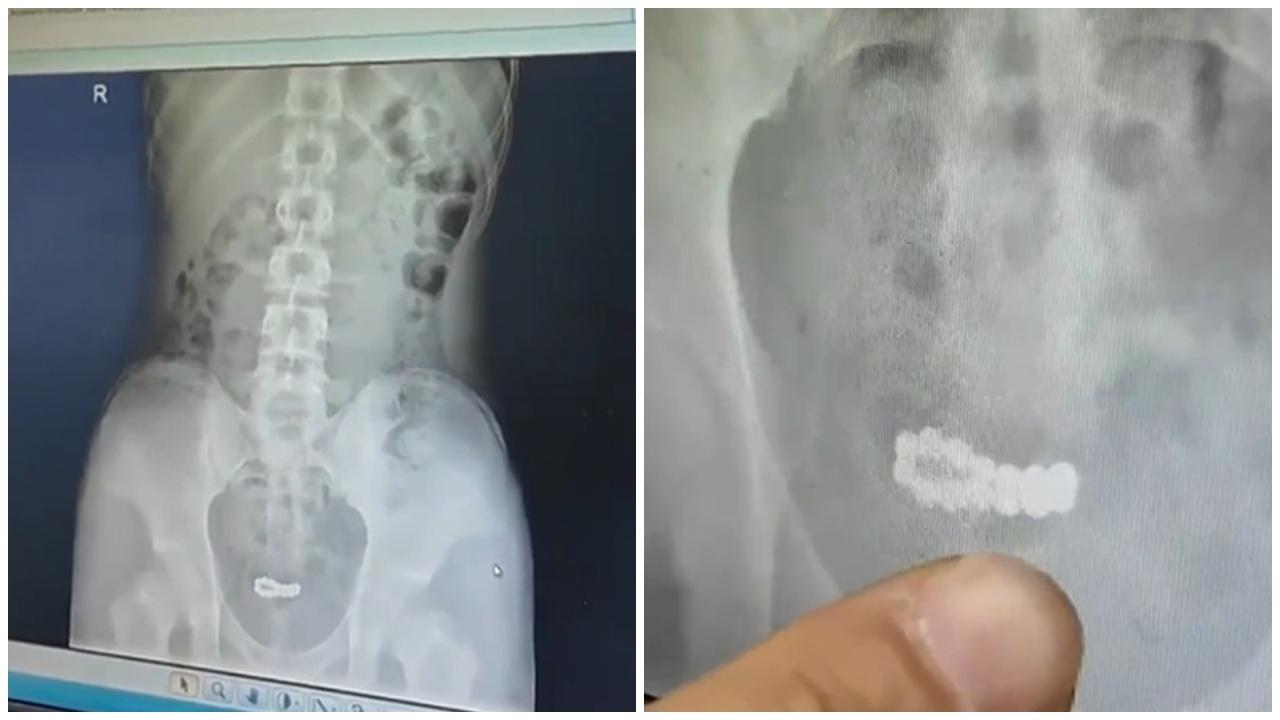

綜合《荔枝新聞》、《新京報》等內地媒體報道,南京一名15歲少年因對身體好奇,將14顆磁力珠塞入尿道,泌尿外科醫生表示,磁力珠雖直徑小於尿道,但取出困難,其金屬材質和強大吸力易造成膀胱損傷。少年就醫時已出現尿頻尿急、腹部疼痛等癥狀,所幸治療及時,最終通過微創手術,成功將磁力珠全部取出。